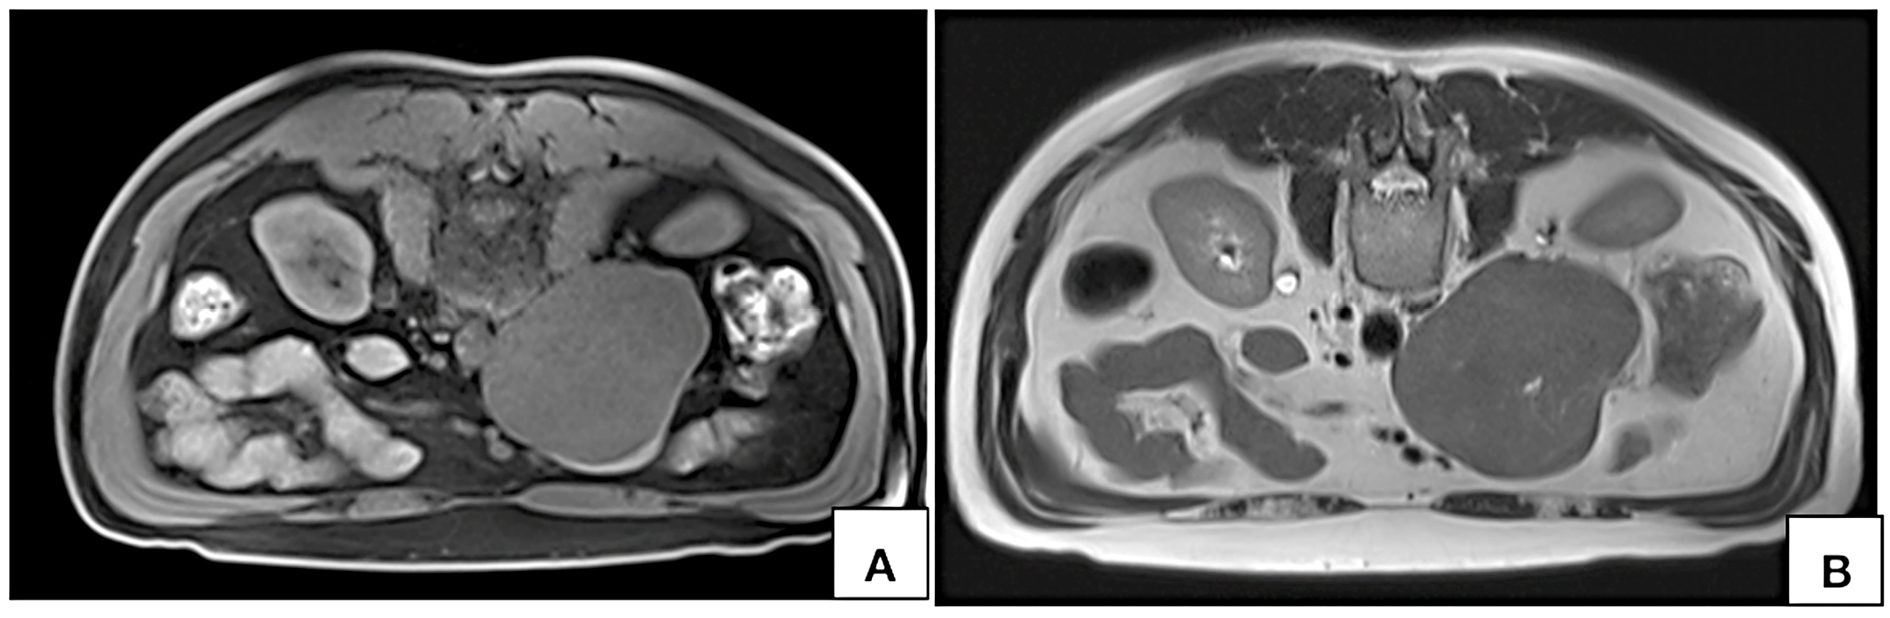

Routine ultrasonographic examination revealed a circumscribed hypoechoic lesion in the upper abdomen measuring 6.6 × 6.3 × 5.9 cm (CC × AP × Tr). For further evaluation, patient underwent computed tomography which revealed a circumscribed retroperitoneal soft tissue lesion in right side of midline, measuring 7.3 × 7.5 × 8.1cm (CC × AP × Tr). The lesion showed inhomogeneous contrast uptake on arterial phase and homogeneous enhancement on portal venous and delayed phases with few nonenhancing areas within. It was abutting the inferior vena cava posteriorly with imperceptible

lumen at the site of maximum contact. However, proximal and distal segments of the inferior vena cava showed normal contrast opacification. Medially, the lesion was in relation to the abdominal aorta. Second and third part of duodenum and head of pancreas were displaced anterosuperiorly. Magnetic resonance imaging (MRI) showed a homogeneously enhancing circumscribed lesion in the retroperitoneum on right side of midline appearing isointense on T1W, hyperintense on T2W showing restricted diffusion. Few cystic areas were seen within the lesion. On prone imaging, the lumen of inferior vena cava was still imperceptible at the site of maximum contact. No obvious intraluminal extension was seen. Whole body positron emission tomography CT revealed mild FDG uptake with a maximum standard uptake value (SUVmax) of 4.1. No distant metastases were found.

On MR imaging LMS of IVC appears hypo- to intermediately intense on T1W and hyperintense on T2W [10, 18, 26]. Due to their malignant nature, these tumors also show diffusion restriction [18]. Similar signal characteristics were observed in our case also.